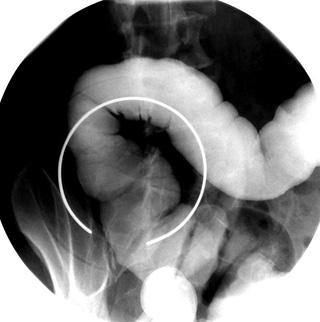

BE RPO patient positionBE Splenic Flexure spot